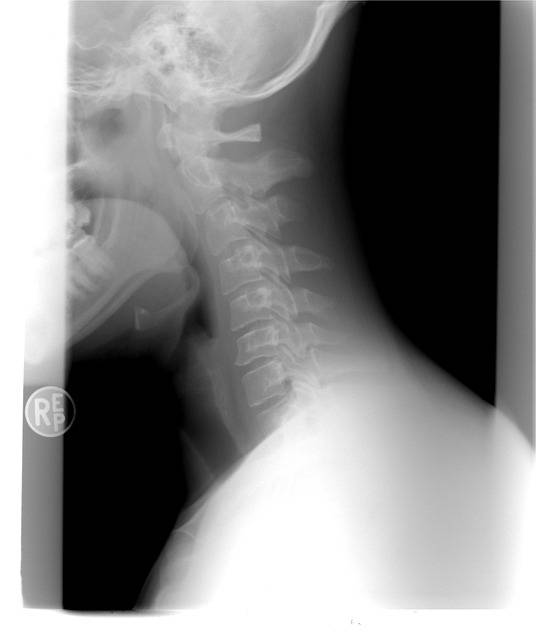

Ostéopathe Marseille, pour un adulte souffrant de traumatisme au niveau cervical, d’un coût du lapin, dans notre cabinet du Cabot dans le 9eme à Marseille.

Ostéopathe Marseille, reçoit ce jour un jeune patient souffrant de douleurs importantes au niveau des cervicales et de la base du crâne, d’un coup du lapin, dans notre cabinet du Cabot, situé dans le neuvième arrondissement de Marseille. Une prise en charge spécifique post-traumatique au niveau d...